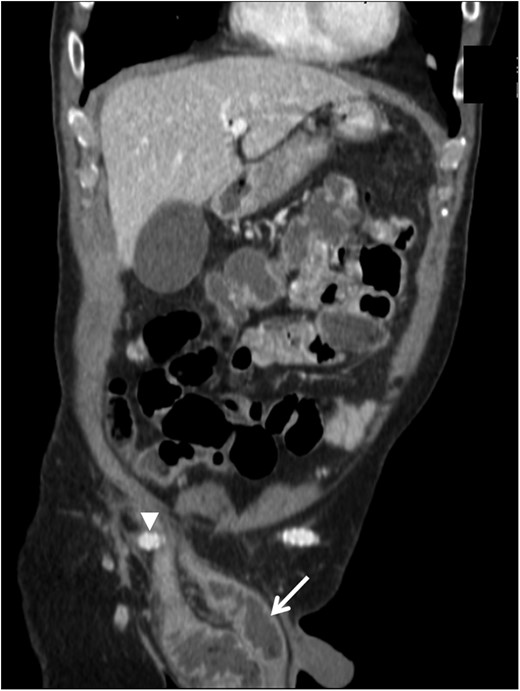

Contrast-enhanced computed tomography coronal image demonstrating the right femorofemoral anastomosis and graft (arrowhead) overlying the hernia sac at the internal ring, with dilated loops of bowel in the hernia sac within the scrotum (arrow).